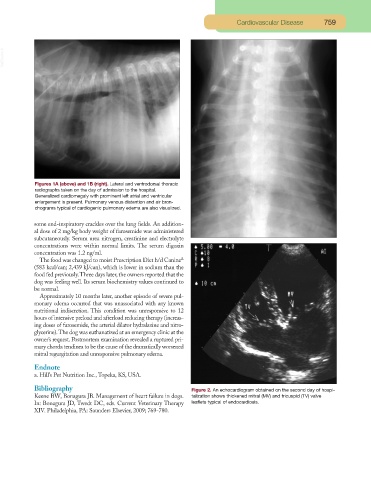

Figures 1A (above) and 1B (right). Lateral and ventrodorsal thoracic

radiographs taken on the day of admission to the hospital.

Generalized cardiomegaly with prominent left atrial and ventricular

enlargement is present. Pulmonary venous distention and air bron-

chograms typical of cardiogenic pulmonary edema are also visualized.